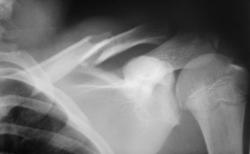

сред3 ключицы. Дистальный отломок смещён каудально на ширину кости.

А какой возраст пациента? Похоже ещё на повреждение головки плечевой кости.

Пациент молодой. Но кроме перелома ключицы тут еще есть ...

Валентин Львович! Думаю, что помимо поперечного перелома средней трети ключицы со смещение отломков на ширину кости и захождением их имеет место разрыв ключично-акромиального сочленения и поперечный перелом акромиального отростка.

Присоединяюсь к д-ру Ермолаеву. Плюс, по-моему, перелом клювовидного отростка.

Считаю, что кроме перелома ключицы, больше ничего нет. Акромион и клювовидный отросток в пределах возрастной нормы. Положение костных фрагментов ключицы допустимое.